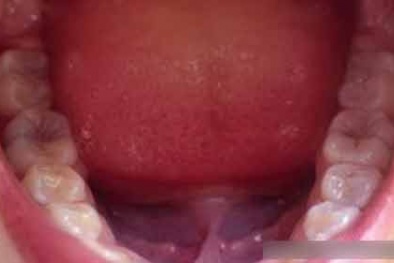

Ung thư ruột kết có thể xuất phát từ... miệng

Vi khuẩn có trong miệng được gọi là Fusobacterium nucleatum có thể làm tăng nguy cơ ung thư ruột kết, theo các nhà khoa học thuộc Đại học Case Western Reserve (Mỹ).